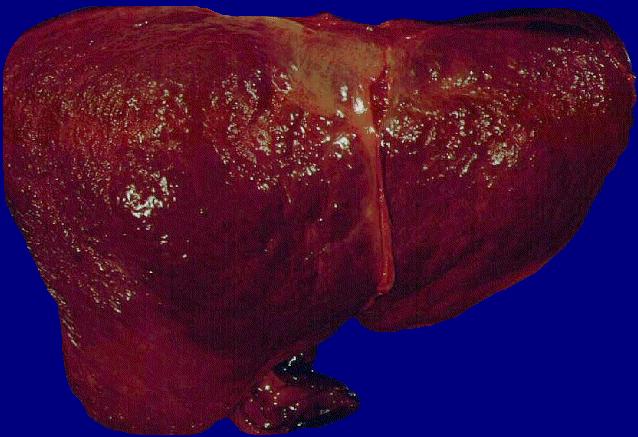

Atrophische Leberzirrhose

Leberzirrhose = Parenchymzerstörung und

bindegewebiger Umbau der Leber mit Aufhebung

der Läppchenstruktur, narbigen bindegewebigen

Faserzügen (Septen) und hyperplastischen

Regeneratknötchen